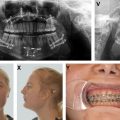

The clinical features of TCS, although variable, are distinct from other craniofacial conditions. Patients with TCS present with a convex facial profile, a prominent nasal dorsum, and a retrognathic lower jaw ( Fig. 1 ). A distinct feature is the ocular and periorbital findings, as described by Collins. Patients typically have dysmorphic orbits, downslanting palpebral fissures, and malar hypoplasia, resulting in an enophthalmic or birdlike appearance. Vision loss, congenital cataracts, and microphthalmia can be seen in severe cases. The most common periorbital abnormalities include (1) thin lower lid skin with lateral canthi malposition, (2) colobomas, (3) periorbital dermoids, (4) attenuated or absent orbicularis oculi muscles, (5) meibomian glands puncta, and (6) atresia of the lacrimal duct. Laxity of the lid margin and absence of lashes are also highly characteristic.

In addition to periorbital dysmorphology, patients with TCS also possess a characteristic dysmorphology of the maxilla and mandible ( Fig. 2 ). These features include decreased sella-nasion-B point, decreased height of the lower third of the face, and a steep, clockwise rotation of the occlusal plane leading to an Angle class II anterior open bite malocclusion. This dysmorphology stems largely from decreased ramal height, and significant condylar hypoplasia is also seen at higher rates among patients with TCS compared with normal controls. , Condylar hypoplasia can secondarily result in temporomandibular joint (TMJ) dysfunction. Importantly, these mandibular and maxillary dysmorphologies frequently cause marked glossoptosis with associated upper airway obstruction; obstructive sleep apnea (OSA) can be seen in as many as 95% of patient with TCSs, and, as a result, some require tracheostomy to ensure airway patency.